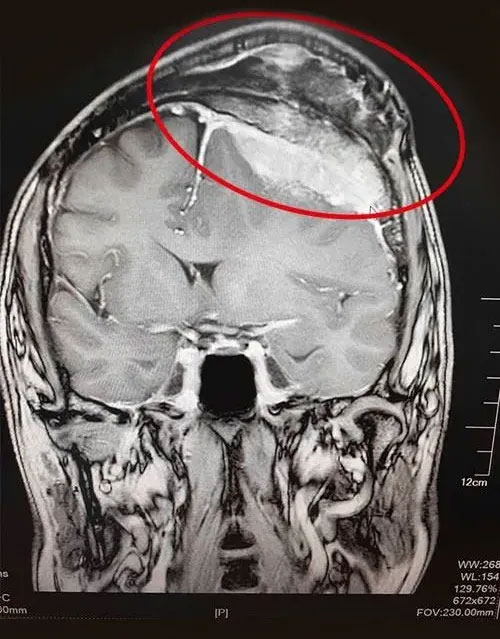

▲ 巨大脑膜瘤图例

脑部肿瘤,尤其是原发性脑瘤和中枢神经系统恶性肿瘤,一直是诊疗难度较大的疾病之一。据柳叶刀子刊《神经病学》(Neurology)研究文章显示,全球较大规模脑肿瘤统计发现,在全球范围内,中国的发病及死亡人数双双位列第一,脑肿瘤防治任重道远。(信息来源:《科技日报》)

在医生为患者全面查体基础上,影像学检查是包括脑肿瘤在内的神经系统疾病的重要诊断方法。主要包括核磁共振成像(MRI)、电子计算机断层扫描(CT),大部分脑肿瘤都可通过上述检查作出定性诊断。颅骨X线平片在脑肿瘤诊断上也具有一定价值,能显示患者颅骨的解剖特点,为开颅手术提供必要的信息。